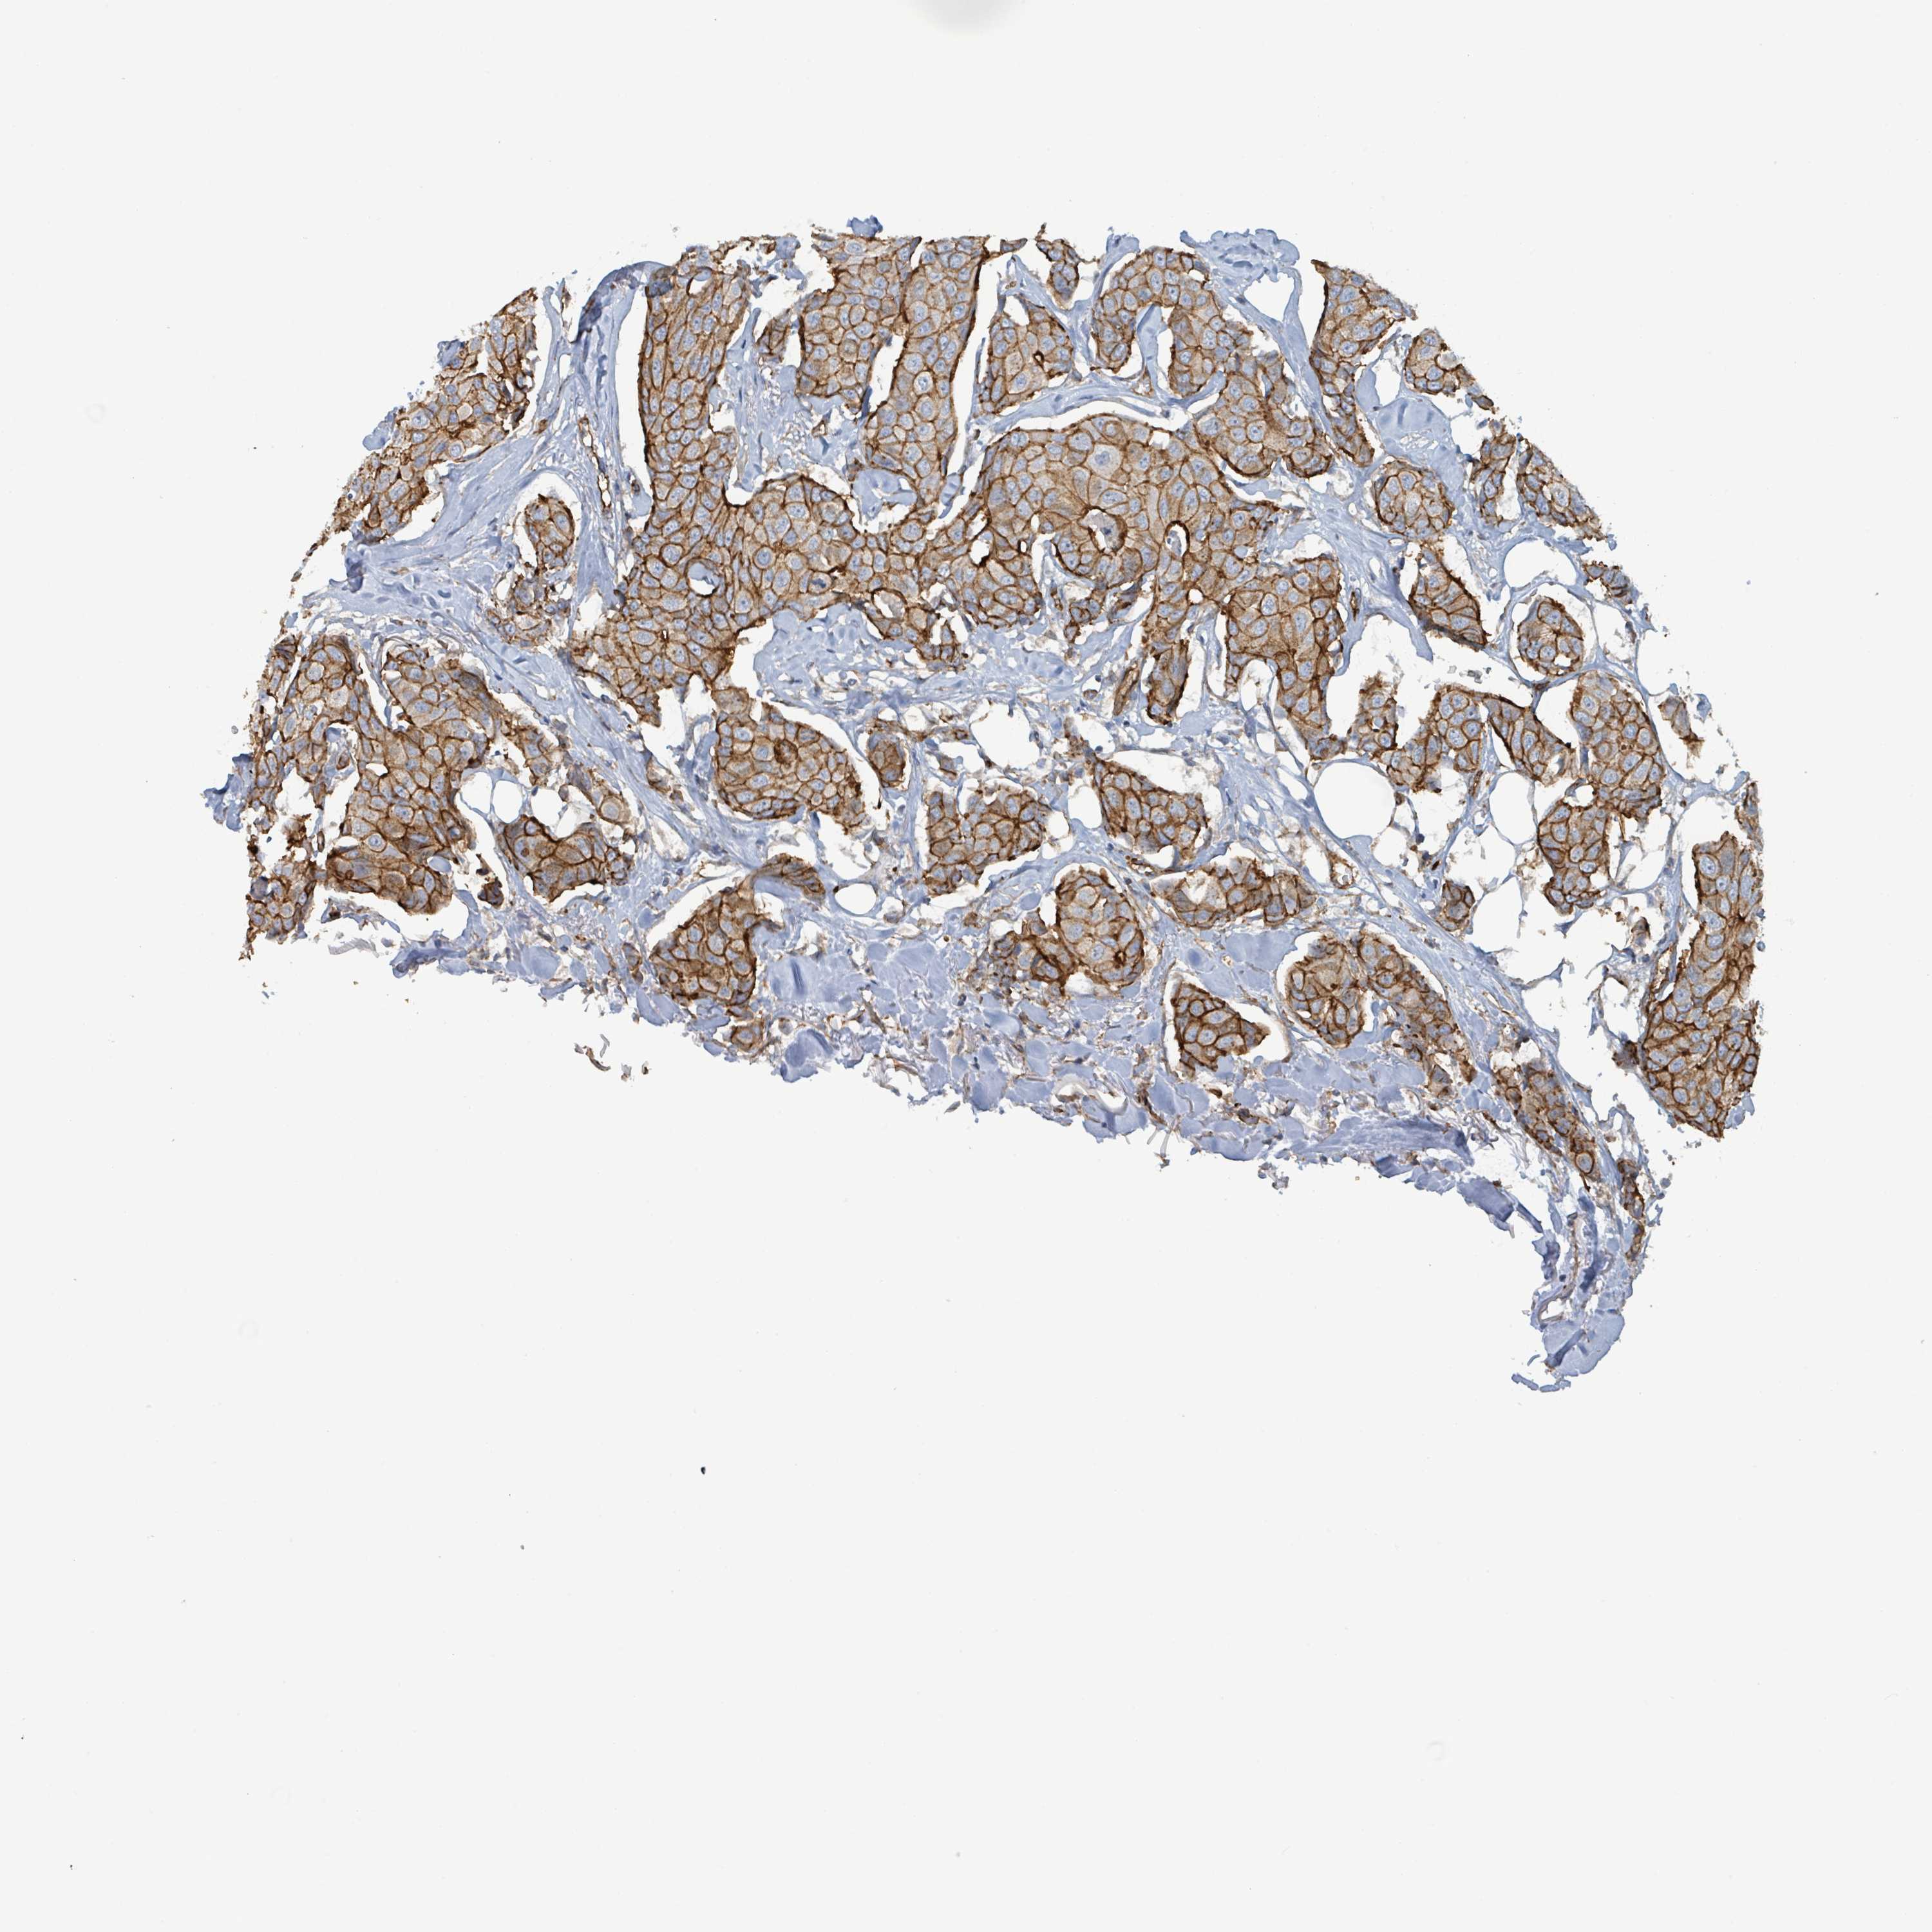

CANCER BREAST CANCER Show tissue menu

BRCA TCGA BRCA VALIDATION PROTEIN EXPRESSION